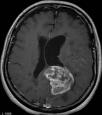

Machine learning has been widely adopted for medical image analysis in recent years given its promising performance in image segmentation and classification tasks. The success of machine learning, in particular supervised learning, depends on the availability of manually annotated datasets. For medical imaging applications, such annotated datasets are not easy to acquire, it takes a substantial amount of time and resource to curate an annotated medical image set. In this paper, we propose an efficient annotation framework for brain MR images that can suggest informative sample images for human experts to annotate. We evaluate the framework on two different brain image analysis tasks, namely brain tumour segmentation and whole brain segmentation. Experiments show that for brain tumour segmentation task on the BraTS 2019 dataset, training a segmentation model with only 7% suggestively annotated image samples can achieve a performance comparable to that of training on the full dataset. For whole brain segmentation on the MALC dataset, training with 42% suggestively annotated image samples can achieve a comparable performance to training on the full dataset. The proposed framework demonstrates a promising way to save manual annotation cost and improve data efficiency in medical imaging applications.

翻译:近年来,由于在图像分割和分类任务方面表现良好,医学图像分析广泛采用了机器学习。机器学习的成功,特别是监督学习的成功,取决于手动附加说明数据集的可用性。对于医疗成像应用来说,这种附加说明数据集不容易获得,需要大量的时间和资源来翻译附加说明的医学成像集。在本文件中,我们建议为大脑MR图像建立一个高效的注释框架,为人类专家提供信息性样图像,供人类专家作说明。我们评估了两种不同的大脑图像分析任务的框架,即脑肿瘤分割和整个大脑分割。实验显示,对于BRATS 2019数据集的脑肿瘤分割任务,培训一个只有7%的附加说明图像样本的分解模型,其性能与全数据集培训的性能相当。对于MALC数据集的整个大脑分割,用42%的附加说明性图像样本进行的培训,可以实现与全数据集培训的类似性能。拟议的框架展示了节省人工注解成本和提高医疗成像应用数据效率的有希望的方法。